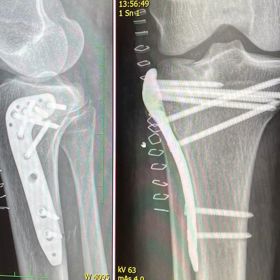

Modelka a influencerka Iveta Kindlmanová se stále nedočkala uzavření svého případu ani dva roky po tragické nehodě, kdy byla sražena řidičem formule na brněnském okruhu. Incident, který se odehrál 10. září 2022, jí způsobil vážná zranění, včetně tříštivé zlomeniny kolene, jak jsme již informovali v předchozím článku.

Rehabilitace a dvě operace, které následovaly, byly bolestivé a náročné. Modelka téměř rok žila s osmi šrouby v koleni, což jí působilo nesnesitelné bolesti při každém kroku. Dnes jí nehodu stále připomíná deset centimetrů dlouhá jizva, kterou si však nejspíš ponechá. „Říkám si, že si ji nechám, aby mi připomínala den, kdy jsem se podruhé narodila,“ říká kráska.